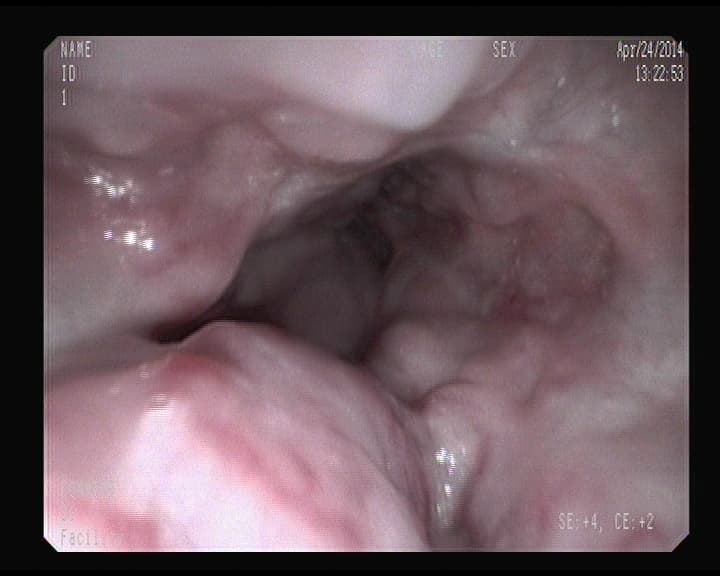

Otra cara de un orificio apendicular normal

Orificio apendicular visto desde el intestino grueso, sin signos inflamatorios.

Visión del orificio apendicular en ciego.

Ese orificio oscuro, es la entrada del apéndice.